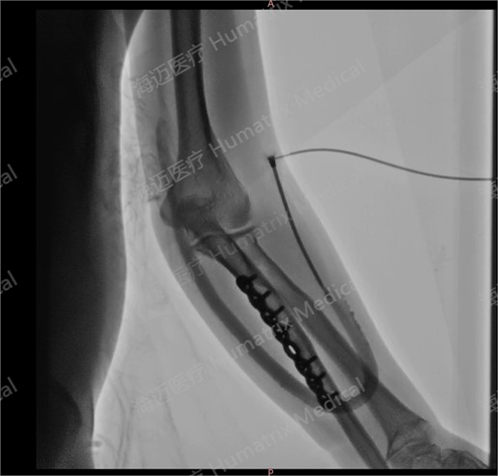

臨床試驗患者使用LineMatrix耐邁通?生物型人工血管長期血液透析,血管造影通暢。

臨床隨訪結果顯示,產品完成植入后,患者術后3月初級通暢率90.9%,累積通暢率100%;術后6月初級通暢率80.8%,累積通暢率100%。人工血管未引發人體免疫反應,無感染及動脈瘤等并發癥發生,產品性能明顯優于ePTFE人工血管,臨床效果優異。